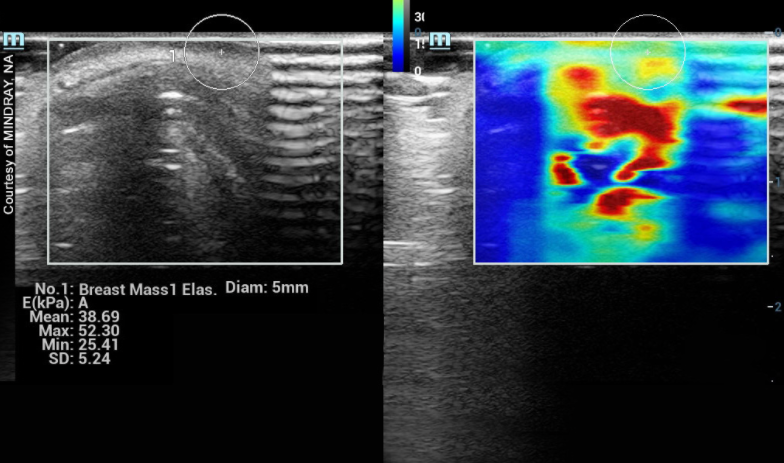

Another example of a dense breast shows the difference between homogeneous white versus the whitish area (see Image 3). This is filled with dark, wormy looking structures, which are the breast glands called glandular tissue. This kind secretes milk and its glands are often dilated. Both fibrous and glandular may appear similar under a mammogram as highly dense areas, but they look completely different under an ultrasound scan. Through ultrasound, we can check for tumors easily through fibrotic dense breasts because it stands out as a black region (or a black hole) within the white area. As shown in Image 3, a black hole could get lost, making it more difficult to image this type of dense breast. In this case, a solution is the use of elastography (see Image 4), which offers visual confirmation as indicated by color data. Elastography can measure tissue density (its hardness or elasticity) within the glandular breast tissue.

Image 4: Elastography of breast mass.